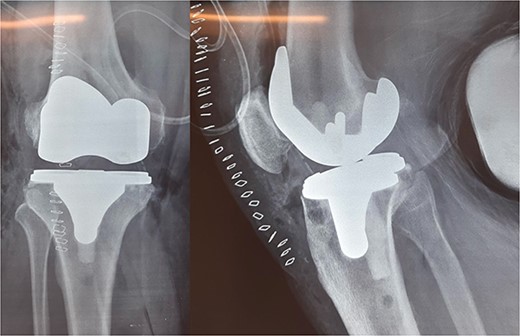

The patient underwent a medial-pivot design TKA (Evolution Medial-Pivot Knee System, Microport, China). Intraoperatively, a full ROM was achieved only after extensive soft tissue and bone releases. The extension gap was limited by significant hamstring spasticity, and a proper extension gap was attained after additional anterior femoral cut. Early postoperative recovery was uneventful (Fig. 2). On the third postoperative day, the patient complained of severe knee pain accompanied by excessive swelling during kinesiotherapy. Clinical examination showed a posterior sag sign at 30° of flexion (Fig. 3). No signs of neurovascular deficit were obvious. A knee X-ray revealed posterior TKA dislocation and a small, non-displaced femoral fracture (Fig. 4). The tibial component was reducible, but redislocation occurred with the knee extended over 90°, indicative of severe instability. Laboratory investigations, including erythrocyte sedimentation rate and C-reactive protein, were normal. A knee arthrocentesis was performed with no substantial findings. Two botulinum toxin injections (200 IU) to the hamstrings were performed without improvement. Local muscle hypertonia was evaluated through a neurological examination and a brain computed tomography scan, with no remarkable findings. The patient’s history included intramedullary nailing of the right femur due to an intertrochanteric fracture 8 months before the TKA.

The external fixator was removed after 6 weeks (Fig. 6), and physical therapy was initiated. The patient’s postoperative course was uncomplicated. One week upon removal, 0°–80° of flexion was achieved through everyday kinesiotherapy. On her last visit, 1 year postoperatively, the patient was ambulatory, with knee ROM of 0°–100° (Fig. 7). No further abnormal neuromuscular signs were observed.